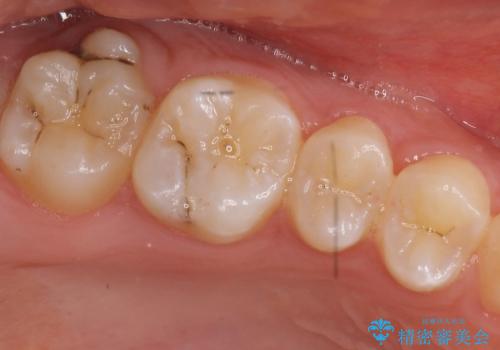

奥歯の虫歯 特殊な形をした歯の治療

- 奥歯が虫歯になり、位置的に詰め物は難しかったため、被せものにする治療を行いました。

頬側に咬頭が一つ多い歯であったのと、歯肉に近い位置が虫歯になっていたため、被せものでしっかり覆う治療を行いました。